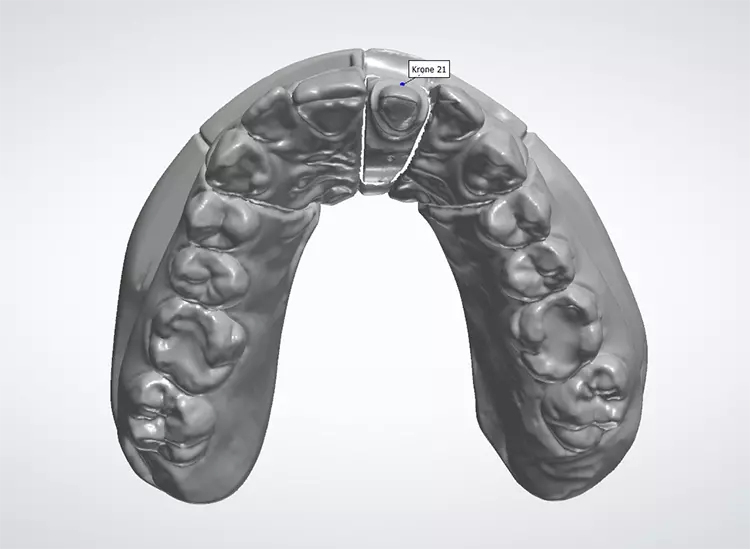

Gleichzeitig wurde mit den initial angefertigten Silikonschlüsseln die anatomische Reduktion des Zahnes 21 visualisiert und die labiale Reduktion in 3 Ebenen bewertet. Die Zielfarbe der Restauration und die Stumpffarbe wurden vor der Abformung für das zahntechnische Labor bestimmt und mit Fotos dokumentiert. Nach Darstellung des Präparationsrandes mittels Retraktionsfaden und Teflonband erfolgte eine klassische Abformung mithilfe eines individuellen Löffels und eines Polyethermaterials (Abb. 11–20).